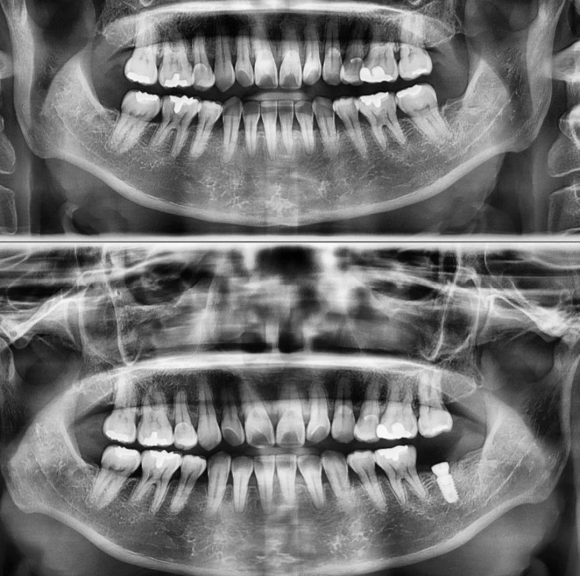

상기 환자 사진 상 오른 쪽 아래 치아의 심한 root fracture로 심각한 증상이 발생하여 치아를 발치하고 GBR(뼈이식) 없이 5개월을 기다린 후 임플란트를 식립 하였습니다. 수술 소요시간은 4분 이었습니다. 성급한 한국인의 특성을 배제하고 충분히 기다린 후 심게 되면 예후 또한 좋을 수 있을 케이스 였...

상기 환자 사진 상 오른 쪽 아래 치아의 심한 root fracture로 심각한 증상이 발생하여 치아를 발치하고 GBR(뼈이식) 없이 5개월을 기다린 후 임플란트를 식립 하였습니다.

수술 소요시간은 4분 이었습니다.

성급한 한국인의 특성을 배제하고 충분히 기다린 후 심게 되면 예후 또한 좋을 수 있을 케이스 였고,

환자분의 인내심이 좋은 수술 결과를 가지고 올 수 있게 도움을 주었습니다.